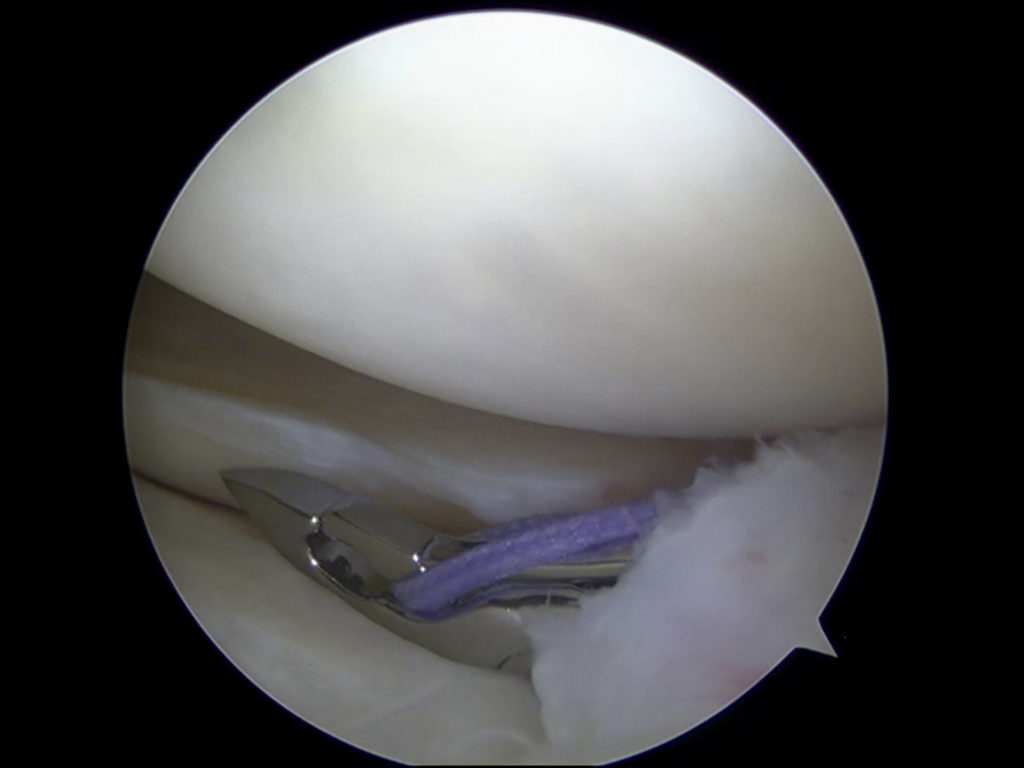

Each knee has two moon-shaped sections of protective cartilage, and each section is called a meniscus. Together, the menisci provide essential cushioning between the top of the shinbone (large lower leg bone) and the bottom of the thighbone (upper leg bone) so that the bones do not rub against one another during movement.

The menisci can tear during strong twisting, high-impact landing, or pivoting motions of the knee. Meniscus tears are a common injury while playing sports such as football, tennis, and basketball, but they can also occur while performing regular household chores.